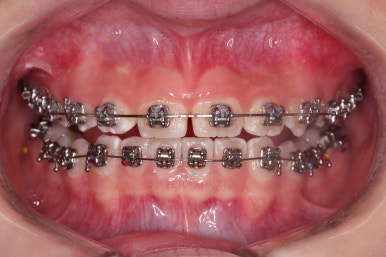

초진 시 입안의 모습입니다.

앞니가 안으로 굽어 들어간 양상인데요. 흔히 "옥니"라고 표현합니다.(뻐드렁니의 반대개념)

전반적으로 치열이 삐뚤삐뚤하고요.

오른쪽 상단 사진을 보시면 어금니의 높이와 앞니의 높이의 차이가 많이 나요.

앞니가 솟구쳐 있는 양상인데요.

그 이유 때문에 어금니로 다물었을 때 위아래 앞니가 많이 겹쳐서 아래 앞니가 아예 보이지 않는 상황이었어요.

이를 "과개교합"이라고 표현합니다.

그리고 전반적으로 아래 치열이 윗니에 비해 뒤로 밀려 있어서, 어금니의 맞물림이 좋지 못하고 듬성듬성해 보이는 상황이었어요.